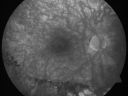

Macular Pucker 20/40 Vision - Pigment Bottom of Photo from Old Retinal Detachment 570 views59-year-old woman blurry vision in the right eye for about the last one or two years. She had cataract surgery in 1981, a retinal detachment repair with scleral buckle in 1988 in the right eye, and then she had lens implants in both eyes, anterior chamber lenses, in 1994. She did start taking Latisse for eyelashes about a year and a half ago.

VISUAL ACUITY: Vision OD is 20/40, OS is 20/20

(4 months later with a short course of antiinflammatory drops and new glasses her vision improved to 20/25)     (0 votes)

OD: Vertical C/D ratio is 0.5. The macula looks slightly irregular. There is also a 2+ epiretinal membrane.

OCT SCAN: The OCT scan shows slight retinal thickening, worse in the right eye than the left eye. The average central foveal thickness in the right eye is 380 microns and the left eye 247 microns.

PHOTOGRAPHS: Photos confirm clinical findings.

FLUORESCEIN ANGIOGRAPHY: FA of the right eye shows minimal leakage at the fovea and optic nerve in the late frames.